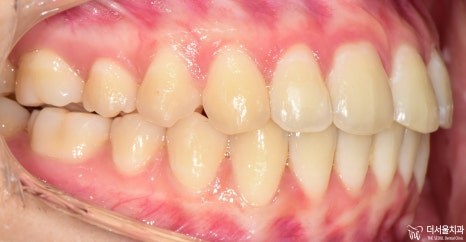

13개월 이라는 교정 치료기간이 소요되었으며, 앞쪽으로 뻐드러져 있던 앞니들도

incisal angle 변화에 따라서 제 위치를 되찾은 것을 볼 수 있습니다.

중첩시킨, 측면 두부 방사선 사진을 보면 확연히 앞니들의 기울기가 변화되는 것을

한 눈에 보실 수 있죠? 아래에는 참조 자료를 남깁니다.